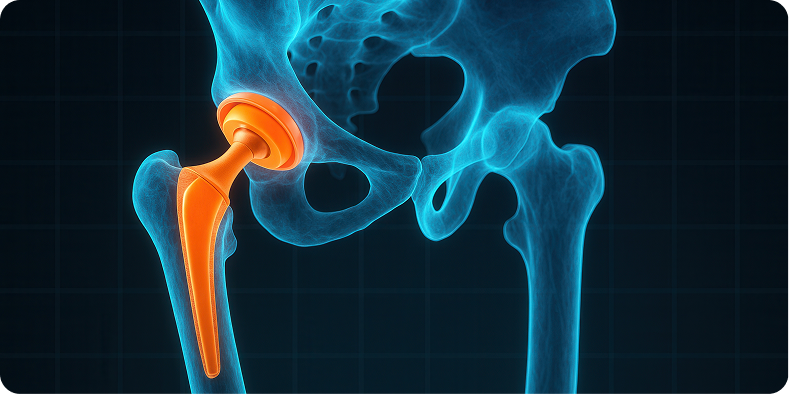

Chirurgia protesica

nei casi in cui la displasia abbia causato artrosi secondaria o dolore invalidante, si esegue l’impianto di protesi d’anca personalizzate con tecniche mininvasive e, quando possibile, assistite da chirurgia robotica per garantire precisione, stabilità e minori traumi.

Grappiolo and Group vanta una consolidata esperienza anche in reinterventi e revisioni protesiche, affrontando con competenza i casi complessi che richiedono una gestione multidisciplinare.